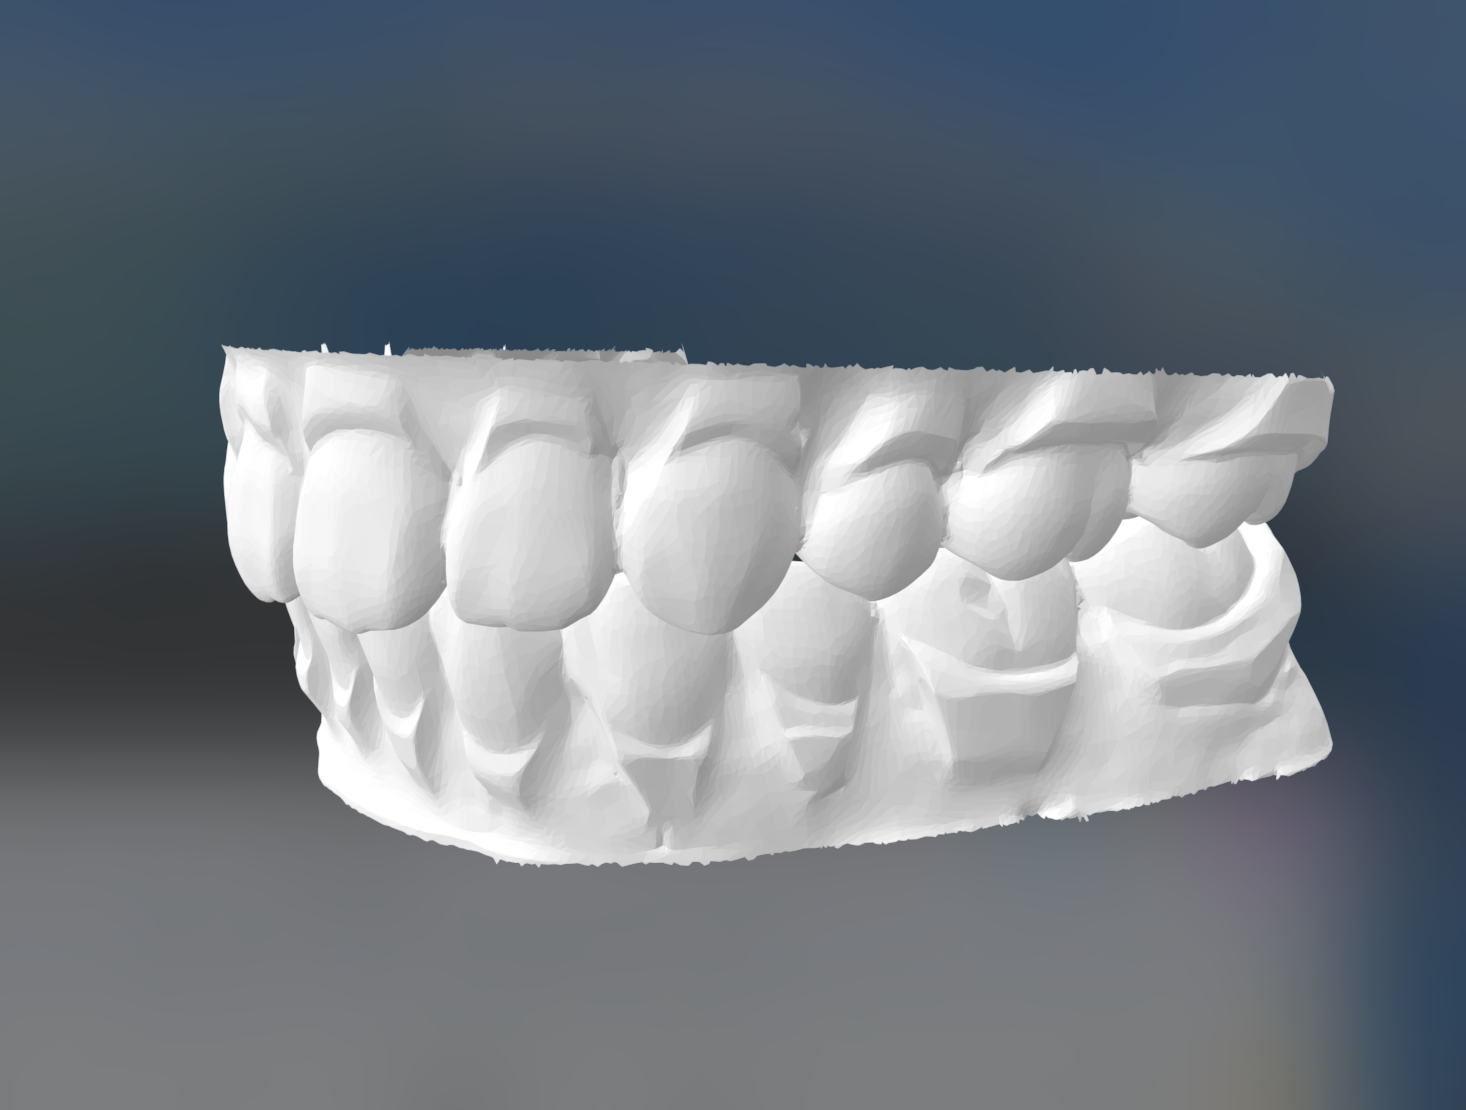

口腔内デジタルスキャナー

口腔内デジタルスキャナーは、口腔内の歯や歯周組織を高精度でスキャンするための装置です。従来の印象法(歯型採得法)に比べて、より迅速かつ正確なデジタルデータを取得することができます。

口腔内デジタルスキャナーは、光学的なセンサーやカメラを使用して、口腔内の詳細な形状や構造を捉えます。これにより、歯や歯列、咬合(かみあわせ)の状態などをデジタル的に再現し、口腔内のデジタルモデルを作成します。

360度様々な角度で口腔内を撮影することができるため、肉眼では確認しにくい個所もしっかりとデータとして取得することが可能です。